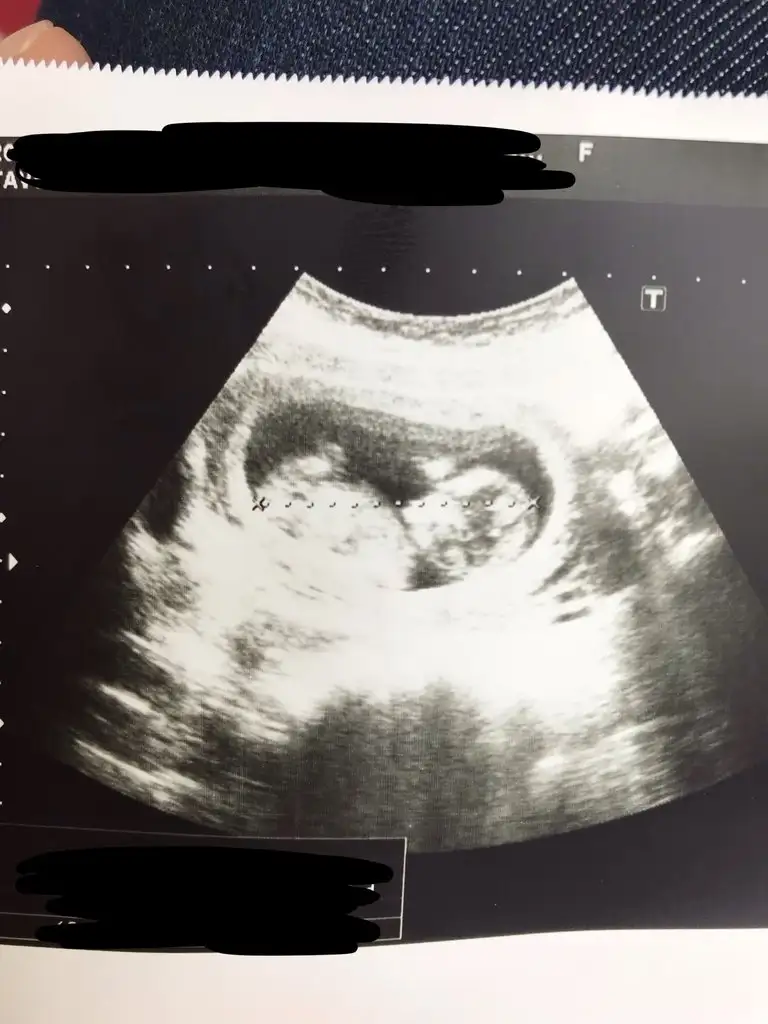

Sagol canim cocuklara biseyler dagitacam simdi oyle demistim :)Çok şükür canım gözünüz aydın